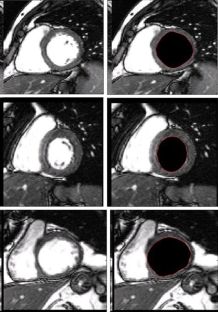

Segmentation of the left ventricle in MRI images is a task with important diagnostic power. Currently, the evaluation of cardiac function involves the global measurement of volumes and ejection fraction. This evaluation requires the segmentation of the left ventricle contour. In this paper, we propose a new method for automatic detection of the endocardial border in cardiac magnetic resonance images, by using a level set segmentation-based approach. To initialize this level set segmentation algorithm, we propose to threshold the original image and to use the binary image obtained as initial mask for the level set segmentation method. For the localization of the left ventricular cavity, used to pose the initial binary mask, we propose an automatic approach to detect this spatial position by the evaluation of a metric indicating object’s roundness. The segmentation process starts by the initialization of the level set algorithm and ended up through a level set segmentation. The validation process is achieved by comparing the segmentation results, obtained by the automated proposed segmentation process, to manual contours traced by tow experts. The database used was containing one automated and two manual segmentations for each sequence of images. This comparison showed good results with an overall average similarity area of 97.89%.

Fig. 3